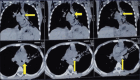

Figure 1

High-resolution computed tomography thorax showing foreign body in left main bronchus